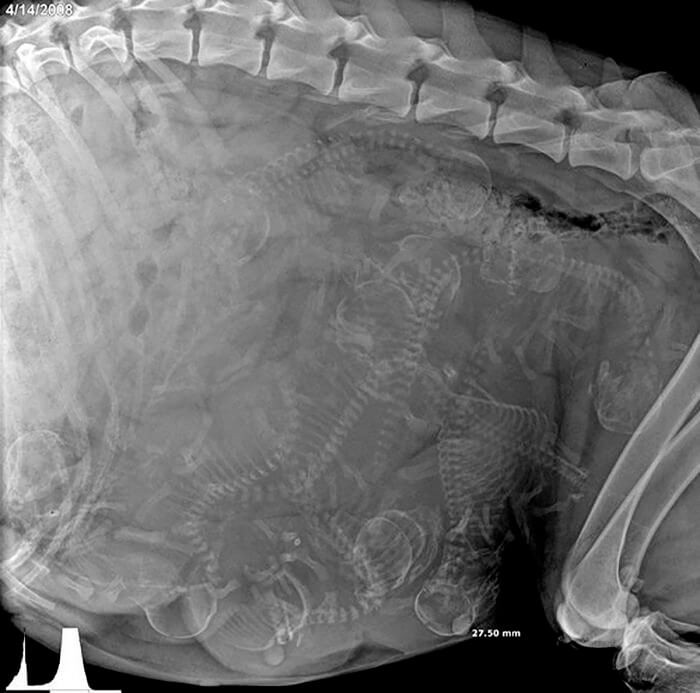

别担心,这是完全正常的

你可能想出各种可能来解释一个巨大身体中无数小骨骼,这么小的地方竟然有那么多的骨头全部挤在一起很震撼!其实是正常的,看看有多少小狗即将降临人间!